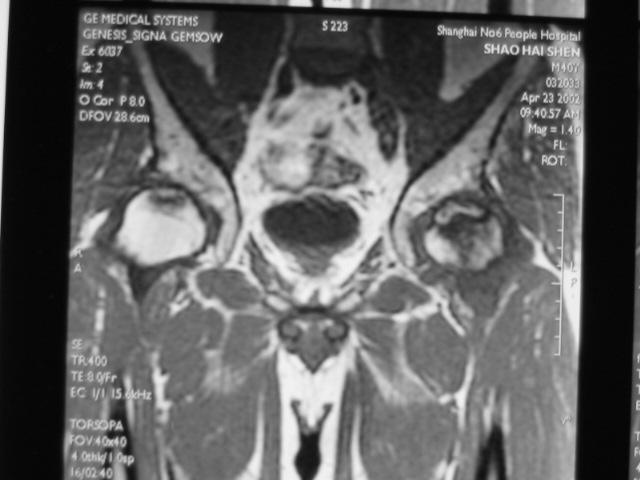

Ⅲ期

髋关节间隙正常,无狭窄。

股骨头表面毛糙、开始变形。

软骨下皮质出现骨折,进一步发展出现轻微塌陷、阶梯状改变。

新月体形成:新月体代表无法修复的坏死骨发生引力性骨折,在T1W上为带状低信号区,T2W上,由于细胞内液渗出或关节液充填骨折线而呈高信号

股骨头表面软骨的完整性受到一定影响。